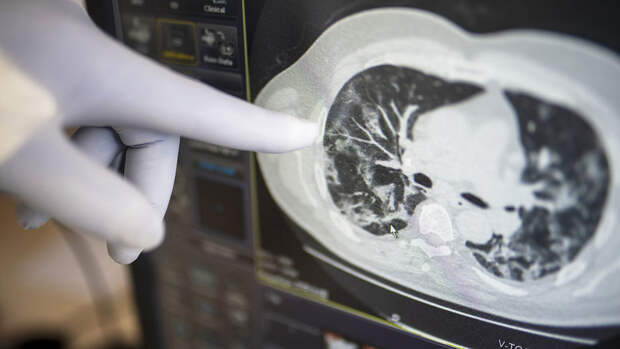

В-третьих, стоит сделать компьютерную томографию - она покажет происходящие при коронавирусе изменения в легких или их отсутствие.